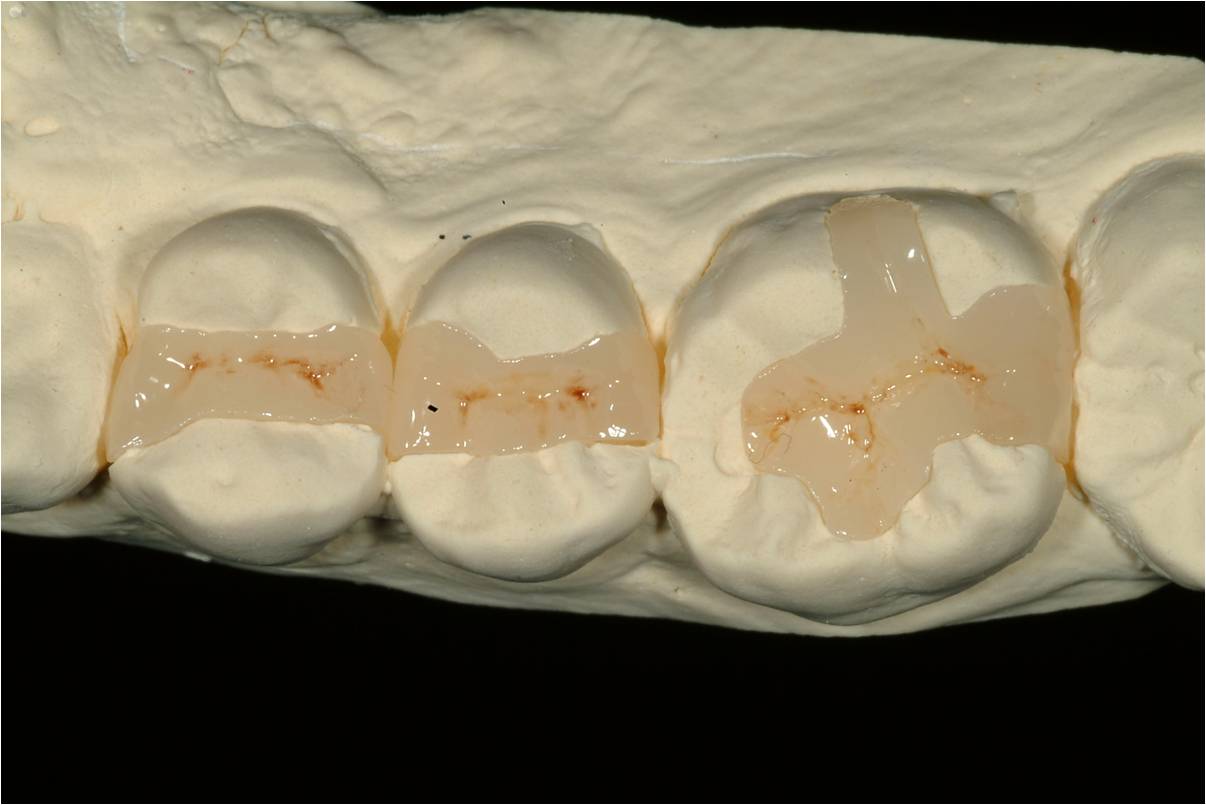

陶瓷崁體製作